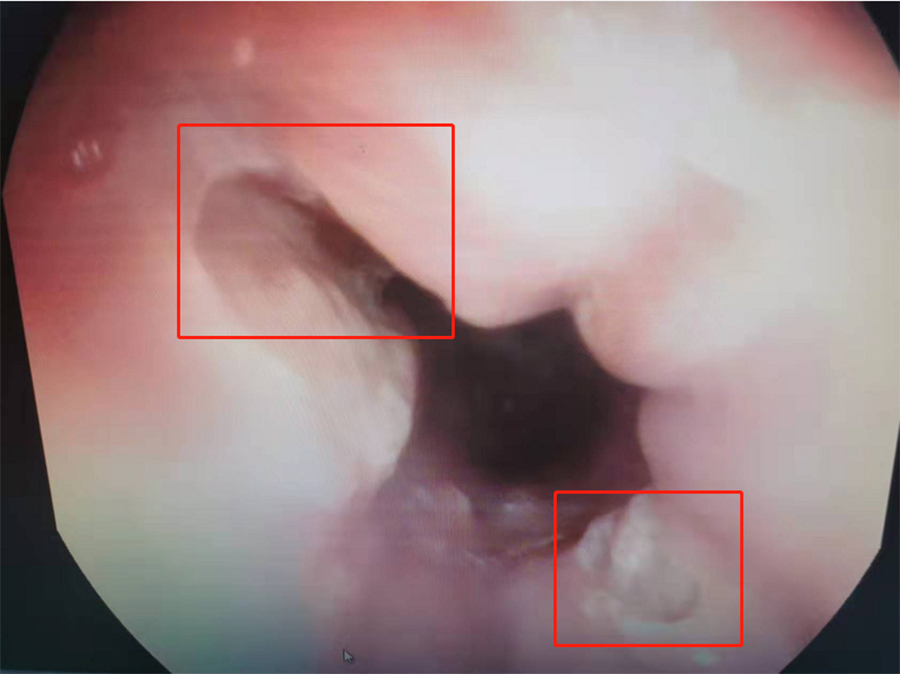

在内镜中心,副主任边鹏为桐桐查体,没发现其上腹胃部区域有压痛。鉴于桐桐腹痛多日,边鹏建议:做胃镜,以明确病因。当胃镜探头进入桐桐食道后,边鹏发现食道下段有两处大面积溃疡,最大处面积达0.3*0.4mm。

溃疡可能是异物所致

临床上,食道溃疡病因很多,常见卡异物后食道损伤,化学性食道损伤、烫伤,部分炎症性肠病也会合并食道溃疡性改变。边鹏根据桐桐食道溃疡对称分布情况,高度怀疑其是误吞异物后造成食道损伤,并有针对性地给出进一步治疗方案:针对食道溃疡,给予口服药物消炎治疗,促进黏膜修复,过一段时间再入院复查。